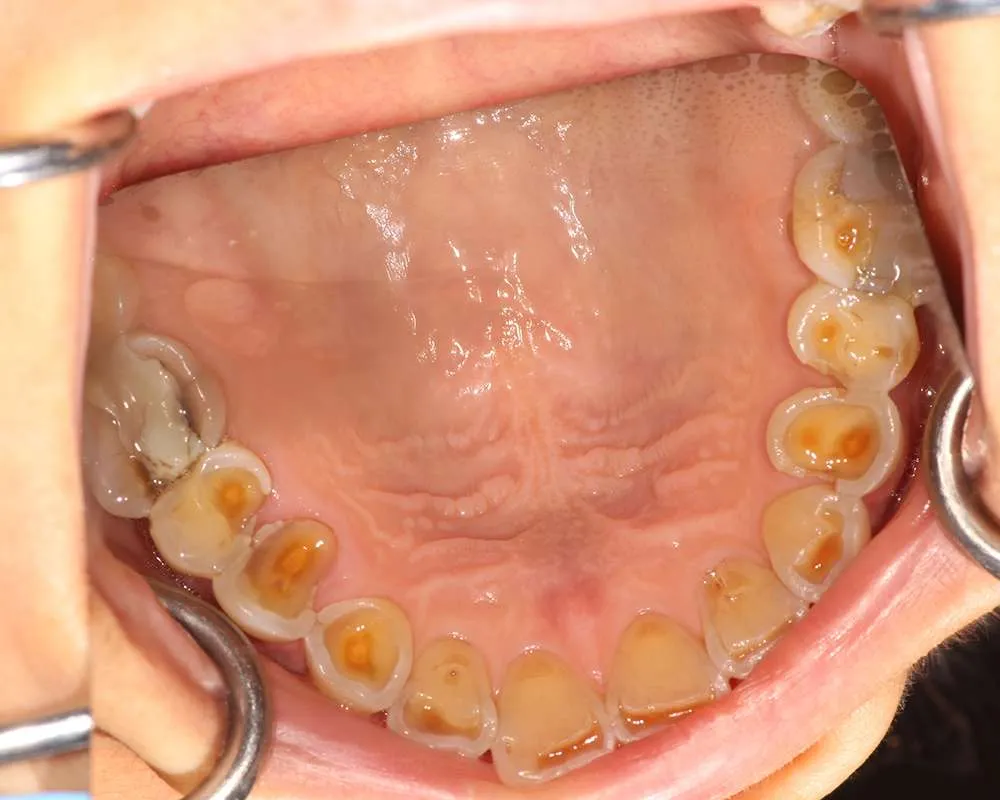

Real Stories, Real Results: Case Studies Showcasing How Our Personalized Approach Transforms Smiles and Lives

Complex Cases

Witness the Remarkable Changes We Can Achieve